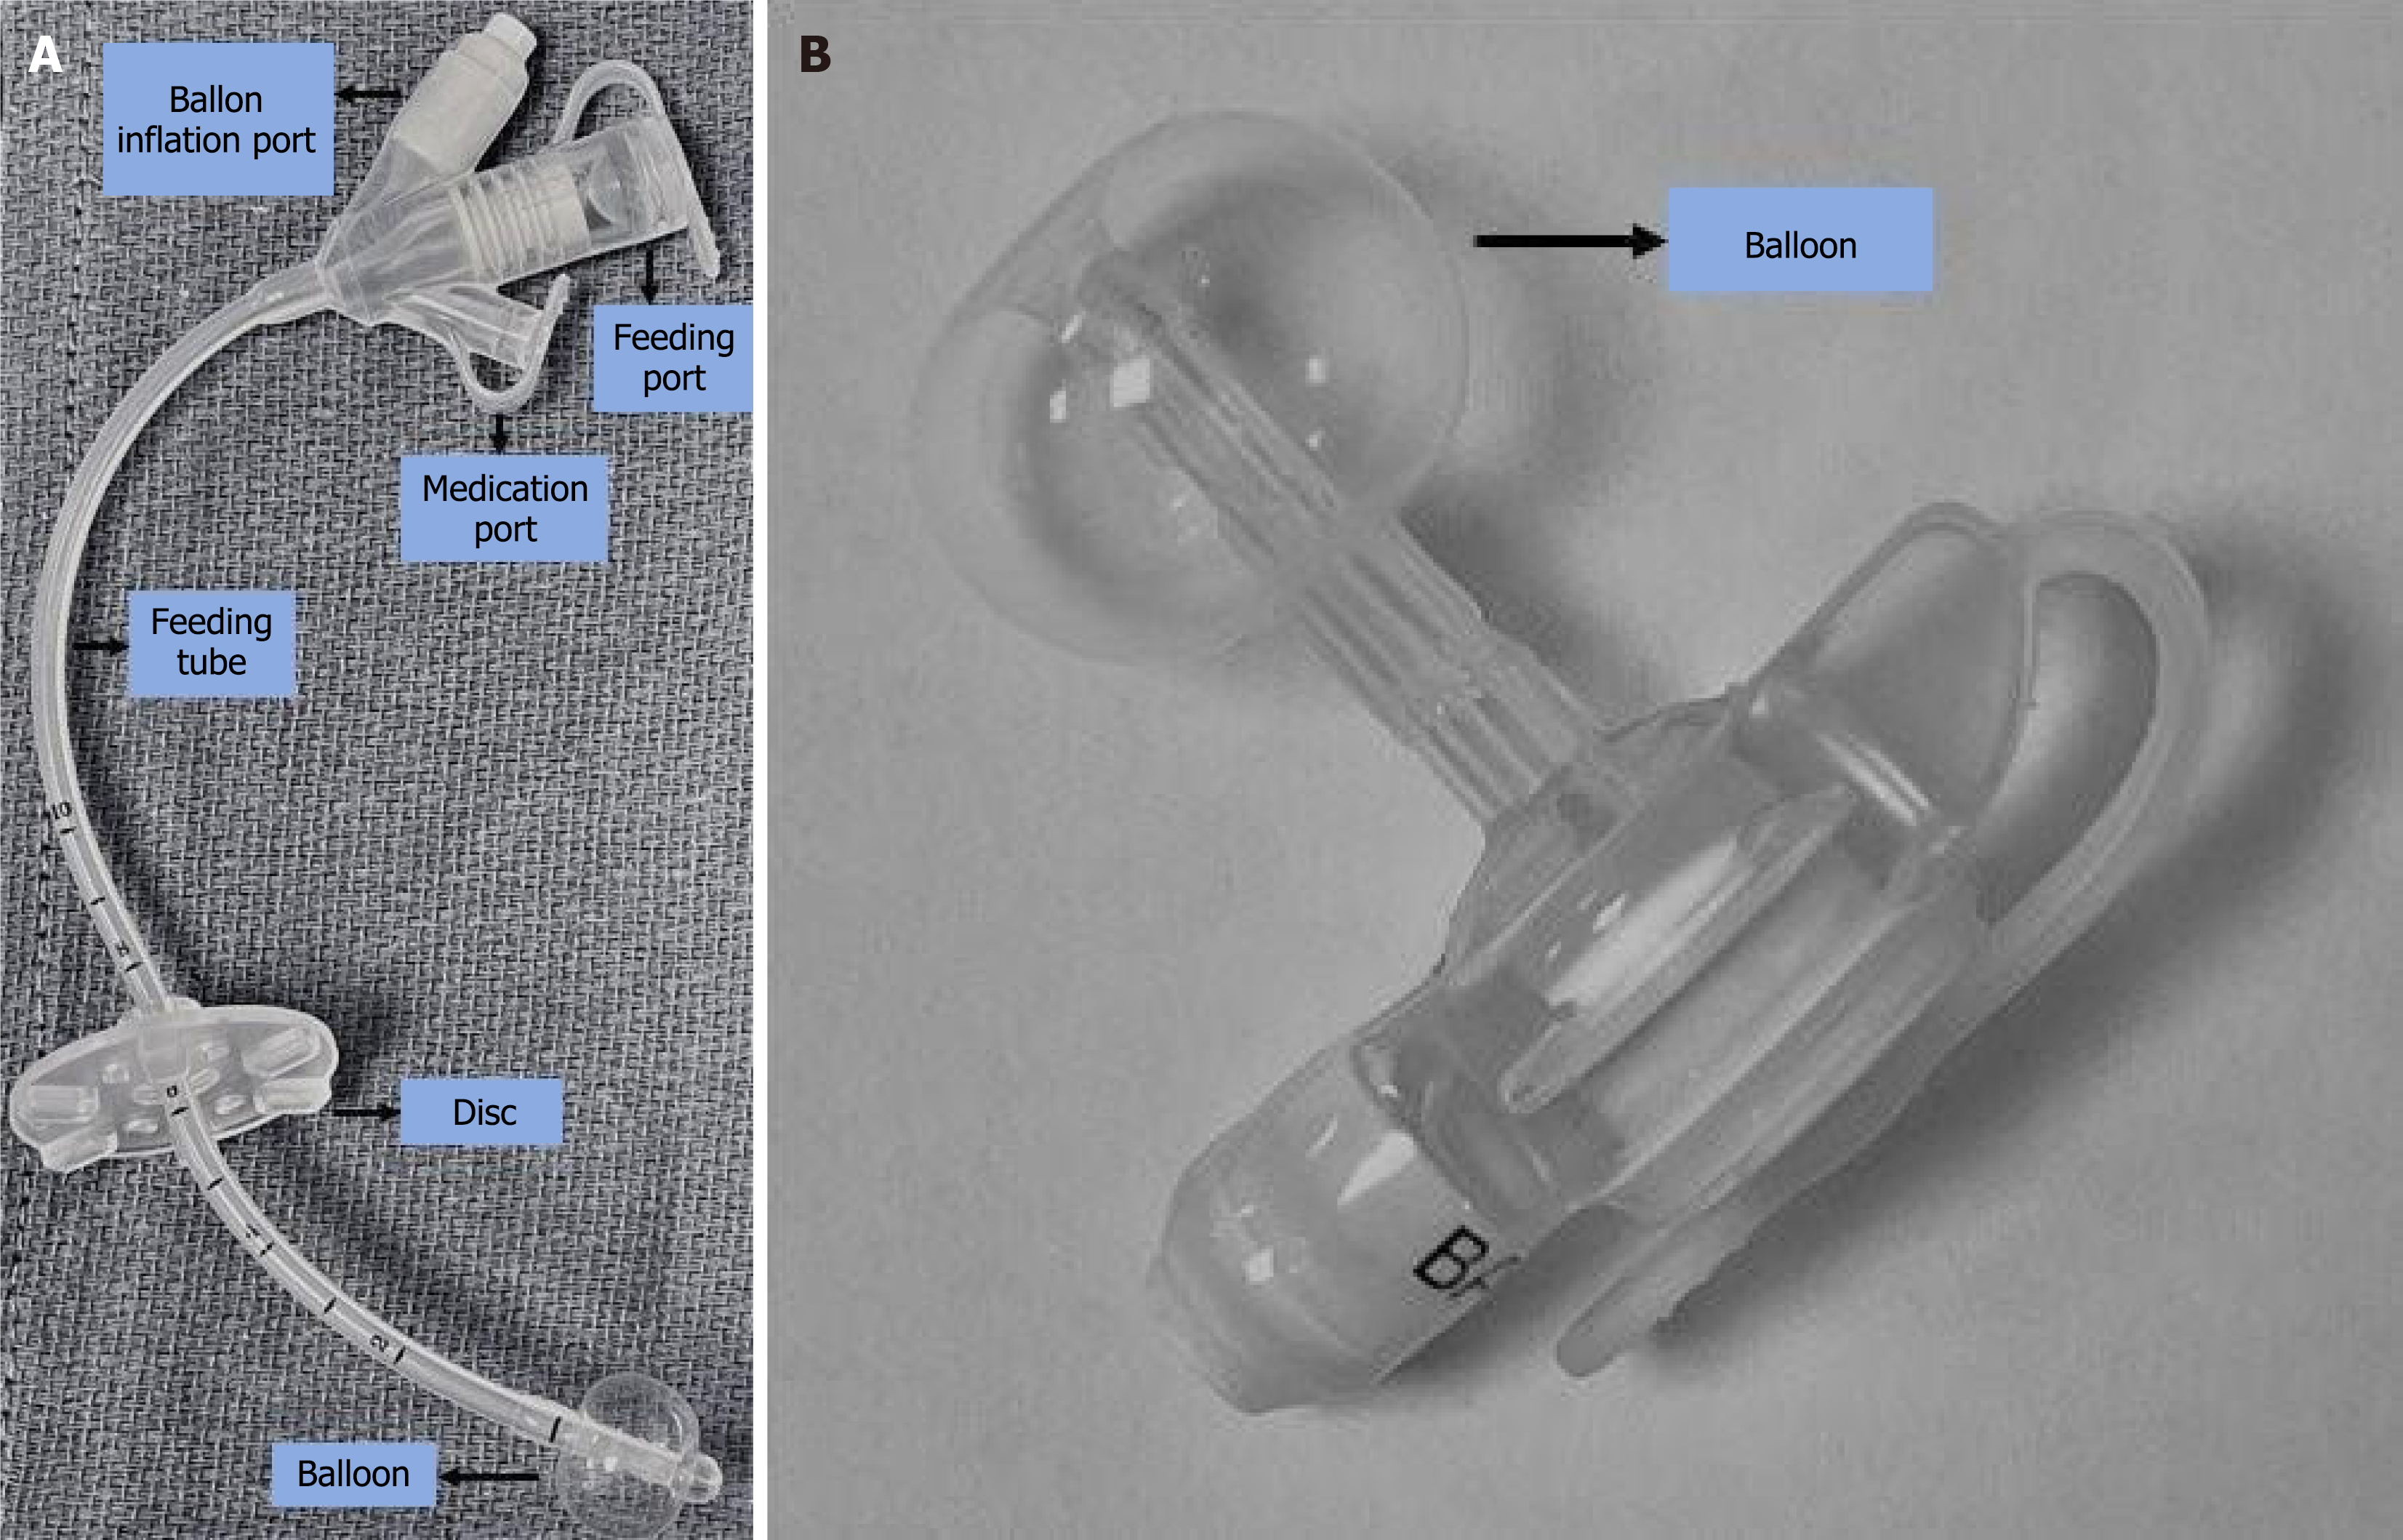

Figure 1 Tube.

A: Standard gastrostomy tube (G-tube); B: Low profile G-tube/ gastrostomy-button.